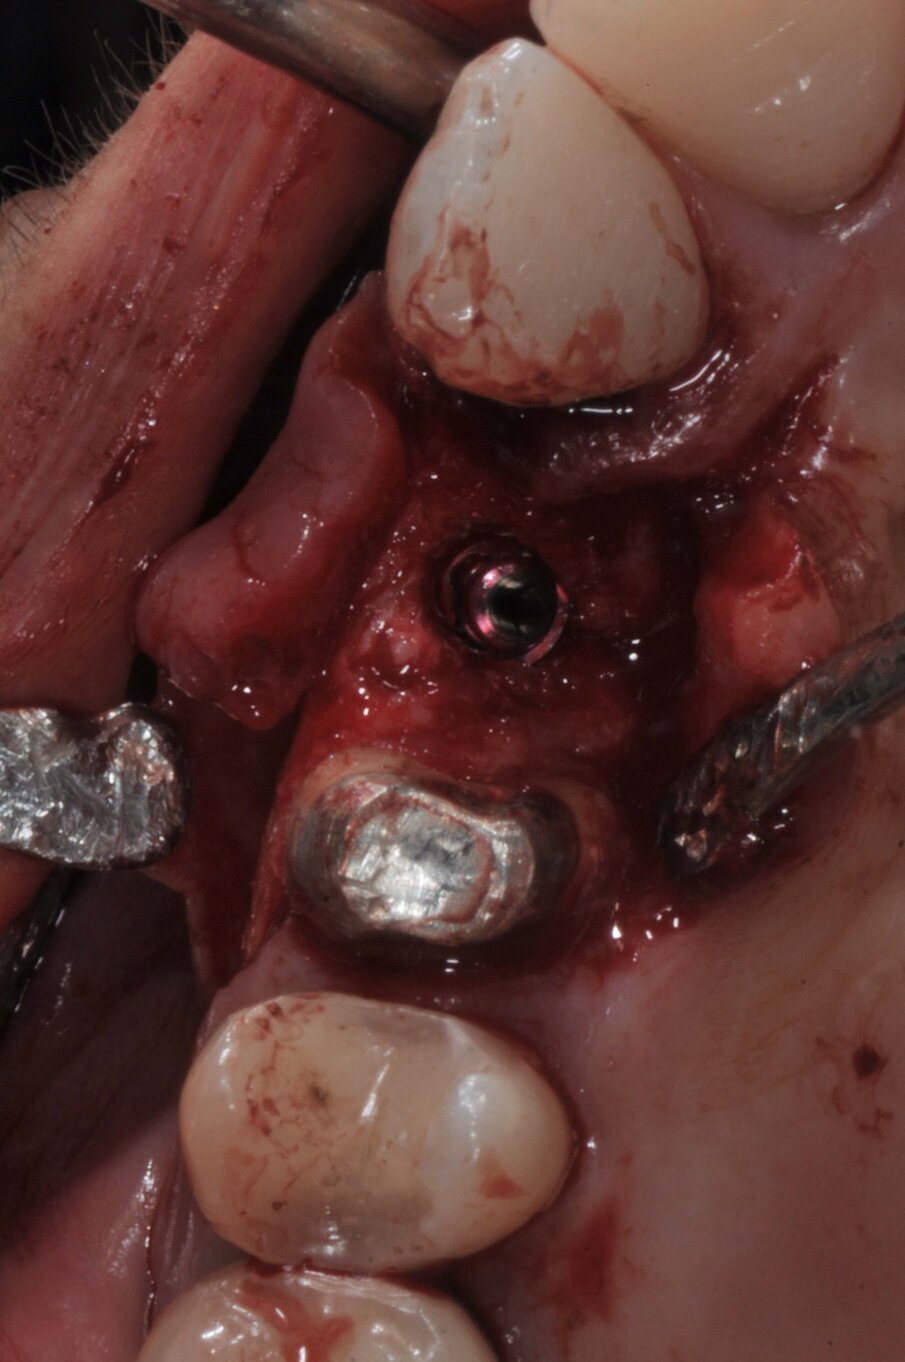

Le corone sui denti 1.3 e 1.4 furono rimosse, il dente 1.3 fu estratto e l’alveolo fu riempito con una membrana di PRGF ottenuta tramite centrifugazione del sangue della paziente con il sistema Endoret e un provvisorio fu consegnato sui denti 1.3 e 1.4 (Fig. 5, 6). Dopo otto settimane fu eseguita una nuova cone-beam e la chirurgia fu pianificata (Fig. 7). Si eseguì un lembo a tutto spessore, fu eseguita l’osteotomia e fu inserito un impianto BTI Core 3.5 × 8.5. Un pilastro Unit fu avvitato e un tappo di guarigione fu applicato. L’osso ottenuto dalla fresatura mescolato con una membrana di PRGF fu applicato sul lato palatale per compensare una piccola deiscenza, una seconda membrana fu applicata sopra l’osso circostante e un innesto di tessuto connettivo prelevato dalla tuberosità fu suturato vestibolarmente per ricreare la bozza canina. Punti di sutura staccati furono eseguiti con un filo in PTFE (Figg. 8-11). Dopo quattro mesi il provvisorio fu rimosso e i tessuti apparivano sani e con un buon spessore di tessuto connettivo vestibolare per garantire la stabilità nel tempo del risultato. Fu eseguita un’impronta con la tecnica del cucchiaio aperto e dopo due settimane furono consegnate una corona in zirconio cementata sul dente 14 ed una avvitata sul denta 1.3. Il profilo di emergenza della corona sull’impianto appariva ideale. Purtroppo, a causa della mancanza del picco osseo sul versante distale del dente 1.2, non si ottenne una papilla di altezza adeguata. Ciononostante la paziente si disse soddisfatta del risultato e rifiutò ulteriori terapie per correggere il difetto residuo (Figg. 12-15).